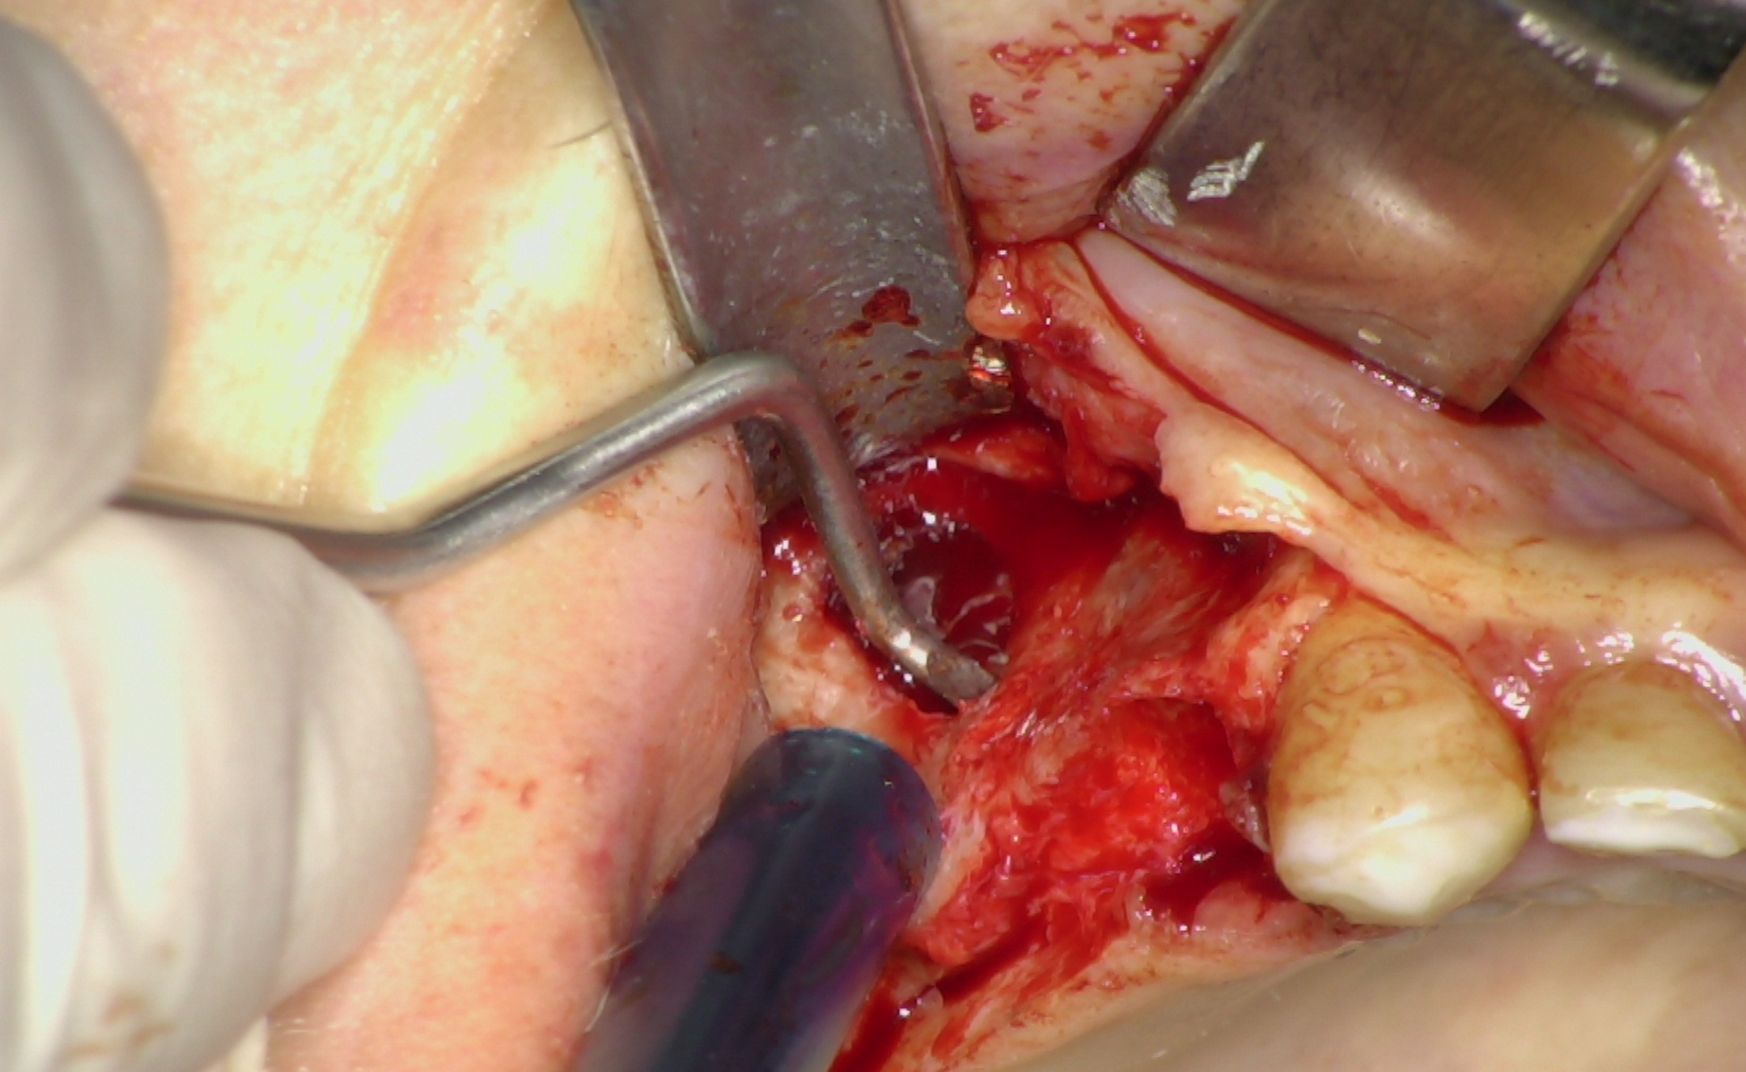

Nei settori posteriori, caratterizzati da significativa atrofia ossea e da pneumatizzazione del seno mascellare, è stato adottato un approccio transinusale. È stata pertanto realizzata una finestra laterale per consentire il sollevamento della membrana di Schneider (Fig. 3), procedura eseguita con particolare attenzione per preservarne l’integrità. Successivamente i siti implantari sono stati preparati con una traiettoria inclinata che attraversa la cavità sinusale, permettendo l'ancoraggio nell'osso basale anteriore. Sono stati quindi inseriti due impianti BT-Rhyno (Fig. 4), progettati specificatamente per l'inserimento transinusale e in grado di garantire adeguata stabilità anche in presenza di ridotto spessore osseo crestale.

Fig. 3 - Membrana di Schneider

Fig. 4 - Impianti BT-Rhyno